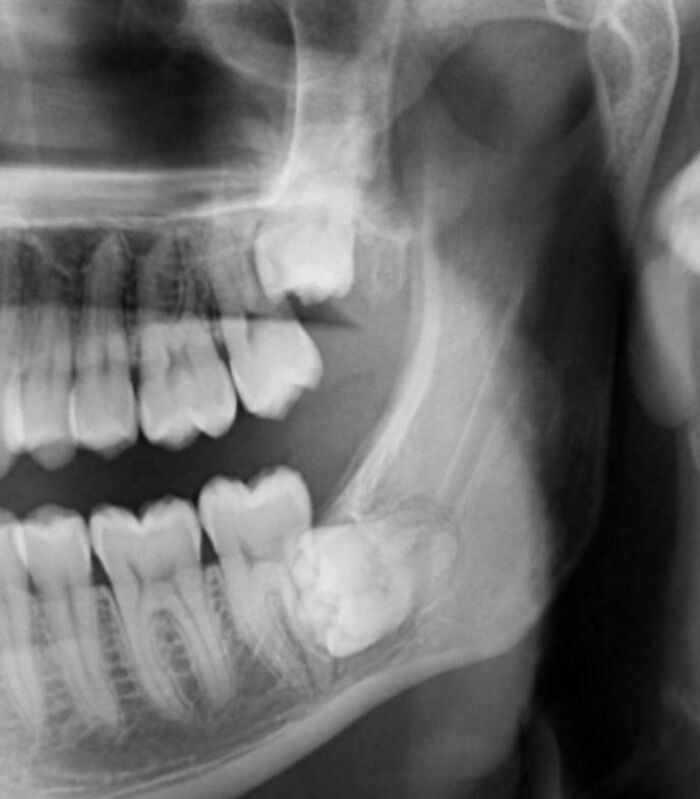

Esto explica el dolor

Eso mismo me pasó a mi, en los dos lados. Cuatro muelas me sacaron de un tirón.